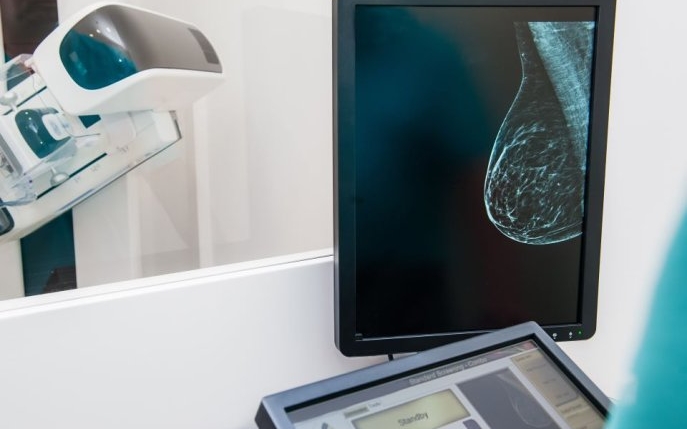

Mamografia este o metodă de investigație radiologică a sânului ce joacă un rol crucial în detectarea precoce a cancerului mamar sau de sân. Această procedură utilizează raze X pentru a crea imagini ale sânului, ceea ce permite identificarea oricăror modificări sau anomalii structurale. De la ce vârstă este ea necesară și de ce, dar și ce presupune o mamografie vei afla mai jos.

Există mai multe tipuri de mamografie: mamografia clasică, mamografia digitală și mamografia cu tomosinteză. Fiecare dintre acestea are caracteristicile sale specifice și este folosită în funcție de necesitățile pacientului și de recomandările medicului.

Mamografia clasică este cea realizată cu un mamograf analog. În acest caz, imaginile obținute vor fi în alb și negru și vor fi imprimate pe segmente de film, similar cu procedura unei radiografii obișnuite. Un alt tip de mamografie este cea digitală, care se diferențiază de cea clasică prin faptul că imaginile sunt obținute pe suport digital. Acest lucru permite medicului să vizualizeze imaginile pe ecranul unui calculator și să le prelucreze pentru a evidenția zonele de interes.

Mamografia cu tomosinteză este un tip avansat de mamografie, cel mai avansat dintre cele disponibile la ora actuală. Acest tip de mamografie permite obținerea unor imagini multiple ale sânului ce vor fi combinate pentru a crea o imagine 3D a acestuia. Această investigație poate fi folosită atât pentru a depista prime semne ale cancerului mamar la paciente asimptomatice, cât și pentru clarificarea diagnosticului în cazurile în care există deja o simptomatologie. La MedLife poți efectua mamografii cu tomosinteză oricând ai nevoie!